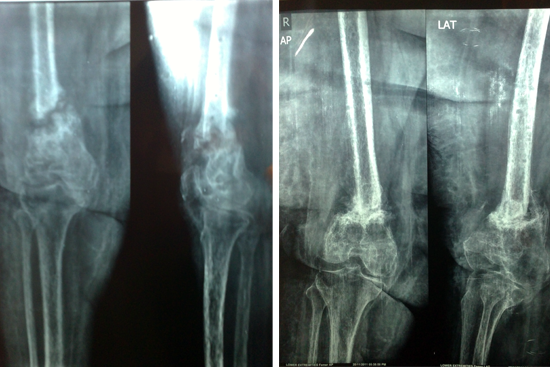

Non Union Femur

Case 1